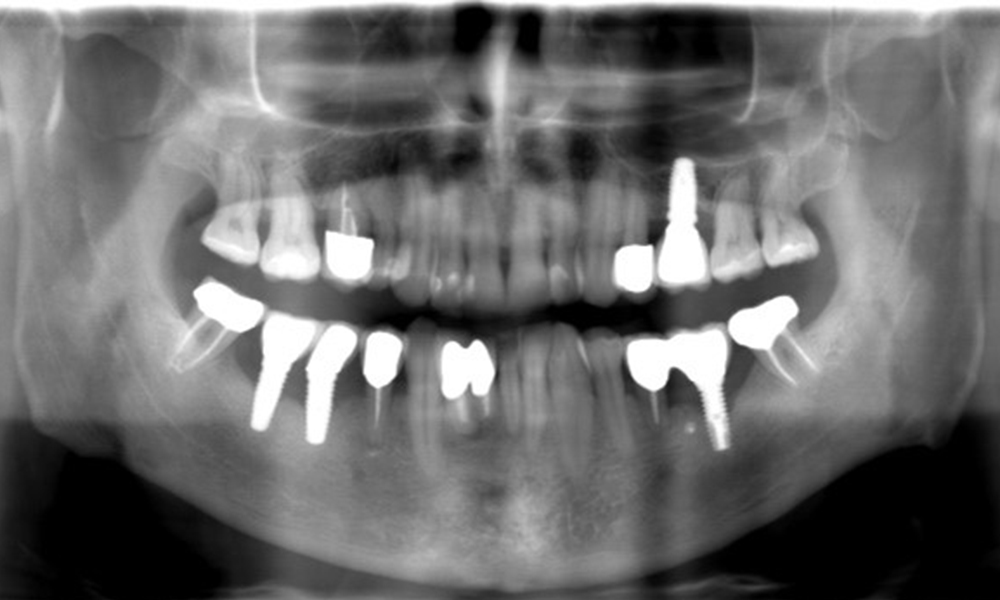

A 52-year-old patient presents at a preventive care session. The patient has no systemic disease and is not taking any medication. He has had various dental treatments and also has two active carious lesions. In addition, the patient has four implants (2nd, 3rd and 4th quadrants). He is revealed to have early periodontal disease (stage IV, grade B). His periodontal condition is stable; a probing depth of Probing depths (ST) of 5 mm is only evident at the implant in region 36. Gingivitis is also identified.

The patient has no particular risk factors with specific dental implications in his medical history. The key factor, therefore, is the requirement in terms of oral health. In this respect, there is evidence of a probing depth of 5 mm at the implant in the 3rd quadrant and, on the X-ray image, increased bone loss. The patient also has currently stable early periodontal disease and two active initial carious lesions.

The X-ray images show the progression of bone loss.

The X-ray images show the progression of bone loss. OPG from 29.06.2020 (left) and OPG from 26.02.2024 (right).

The X-ray images show the progression of bone loss in the area of the implant in region 36: dental film from 11.02.2021 (left) and dental film from 18.01.2024 (right).